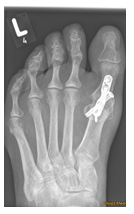

Begradigung durch Stabilisierung

Bei fortgeschrittener Fehlstellung kommt es zu einer Instabilität des sog. TMT 1 Gelenkes, welches die Belastbarkeit der großen Zehe beim Gehen erschwert. Daher erfolgt eine Stabilisierung in diesem Bereich (Arthrodese des TMT I Gelenkes). Der Zeh wird hierbei durch die Entnahme eines kleinen Knochenkeils begradigt. Auch hier wird ein verkürzter Muskel gelöst, um die Stellung des Zehs langfristig zu sichern. Meist wird diese OP-Methode mit einer Osteotomie nach Akin kombiniert (s.o.).

Nach der Operation ist in einem Vorfußentlastungsschuh zunächst eine Teilbelastung an Stützen für 4 Wochen notwendig, solange sollte die Thromboseprophylaxe erfolgen. Anschließend kann im Vorfußentlastungsschuh ohne Stützen voll belastet werden, nach insgesamt 8 Wochen nach der Operation kann wieder ein Normalschuh benutzt werden.